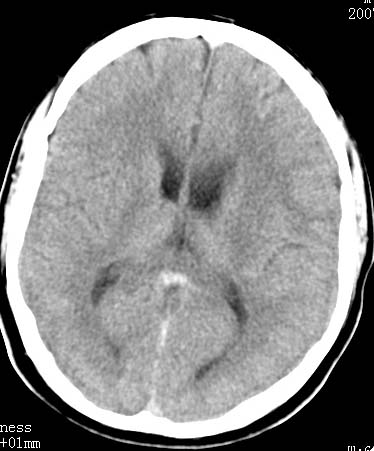

以下是引用clj20在2007-8-29 9:47:00的发言:[br]蛛网膜下腔出血,左侧额叶不均匀密度影,占位效应明显,界限不清。支持:占位性病变,建议增强!

以下是引用xulianj在2007-8-29 20:15:00的发言:[br]蛛网膜下腔出血,左侧额叶不均匀密度影,占位效应明显,界限不清。支持:占位性病变,建议增强!

以下是引用jiangjing在2007-8-29 14:33:00的发言:[br]左侧额叶不均匀密度影[低密度为主,边缘见等密度环环绕]占位效应明显,界限不清。支持:占位性病变,建议增强! [br][br]